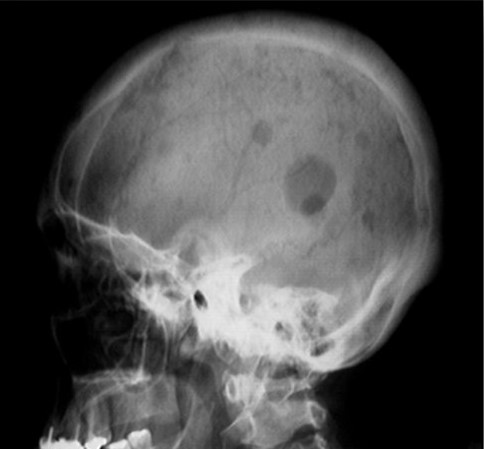

Case discussion The patient is suffering from multiple myeloma. Multiple myelomas represent a malignant proliferation of plasma cells derived from a single clone. The plasma cells in a normal individual are end-stage cells that secrete specific antibodies for a few days and then die. In contrast, the plasma cells in an individual with multiple myeloma […]